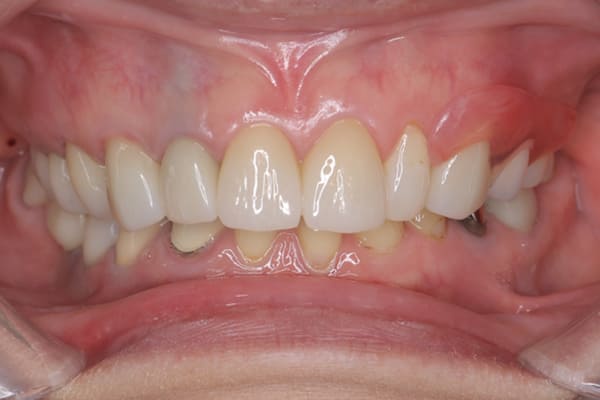

治療前後の口元の比較

こちらは、口を少し開いた時の治療前と治療後の

口元です。

正面から見た時にクラスプが目立たないように、

歯ぐきになじむ素材にて入れ歯を製作し、痛くなく自然に馴染み快適に生活を送れるようになりました。